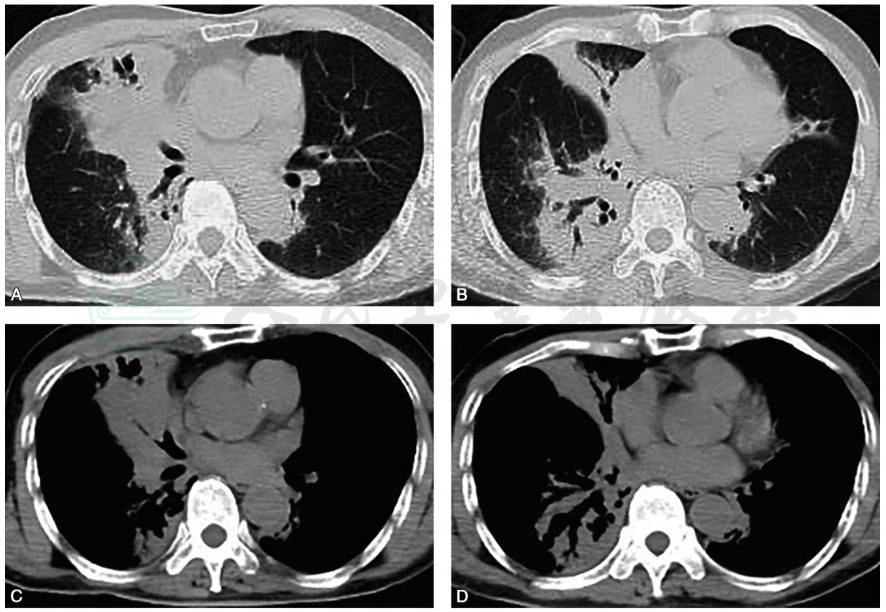

胸部CT扫描(2016-06-20):右肺中叶、右肺下叶后基地段可见大片肺实变,伴支气管充气征及牵拉性支气管扩张(图1)。

图1 胸部CT扫描示:右肺大片实变影,左肺下舌段和下叶可见少量实变影(A、B);纵隔窗可见支气管充气征和典型的牵拉性支气管扩张(C、D)